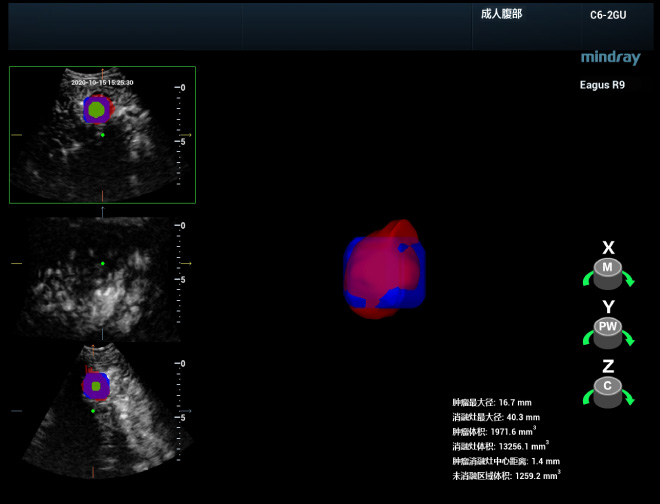

Meilleure exactitude du diagnostic clinique

La rÃĐalisation d'une ÃĐvaluation exhaustive et immÃĐdiate aprÃĻs l'ablation est essentielle pour dÃĐtecter les tumeurs rÃĐsiduelles et effectuer immÃĐdiatement un traitement complÃĐmentaire, afin d'amÃĐliorer le taux d'ablation complÃĻte et d'ÃĐviter la survenue d'une progression locale. L'ÃĐquipe du professeur Xie peut rÃĐaliser une ÃĐchographie?3D du site d'ablation juste aprÃĻs l'intervention, puis la fusionner avec les donnÃĐes de l'ÃĐchographie?3D pour obtenir une image complÃĻte. Elle peut ainsi dÃĐterminer si le site d'ablation couvre la marge de sÃĐcuritÃĐ de la lÃĐsion dans l'ensemble de l'espace?3D et s'il reste une partie de lÃĐsion ou si l'ablation est insuffisante. En outre, la visualisation de la segmentation tomographique et de la reconstruction volumique 3D de l'image de fusion permettent de visualiser plus clairement l'emplacement spatial de la zone nÃĐcessitant un traitement complÃĐmentaire et sa relation avec les organes vitaux environnants.